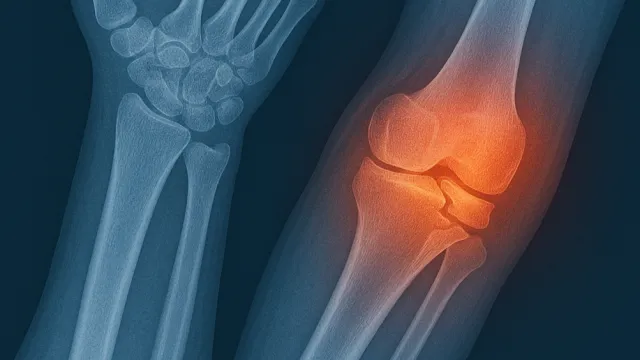

Diz kireçlenmesi (diz osteoartriti), eklem kıkırdağının aşınması sonucu ağrı, hareket kısıtlılığı ve yaşam kalitesinde ciddi düşüşe yol açar. İleri ev...